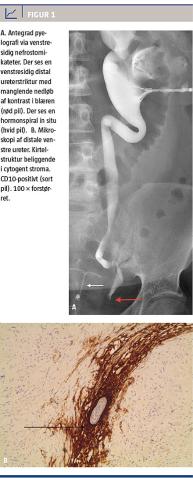

Da infektionen var under kontrol, blev der foretaget antegrad pyelografi, hvor man fandt en 2 cm distal venstresidig ureterstriktur lige før ureters indløb i blæren (Figur 1A). CT af abdomen viste atrofisk venstre nyre. Der blev foretaget forsøg på diagnostisk ureteroskopi med biopsi, men denne kunne ikke gennemføres pga. den udtalte ureterstriktur.

forblev ukendt trods såvel gynækologisk som organkirurgisk udredning. Efter otte ugers insufficient behandlingsrespons på infektionen og svær distal ureterstriktur blev der foretaget venstresidig nefroureterektomi. Operationen forløb ukompliceret, og patienten blev udskrevet efter få dage. Patologisvaret viste, at venstre nyre havde kronisk inflammation og akut abscederende inflammation. I den distale del af ureter fandtes inflammatoriske forandringer, fibrose og små øer af endometroidt væv, hvilket er diagnostisk for ureteral endometriose.